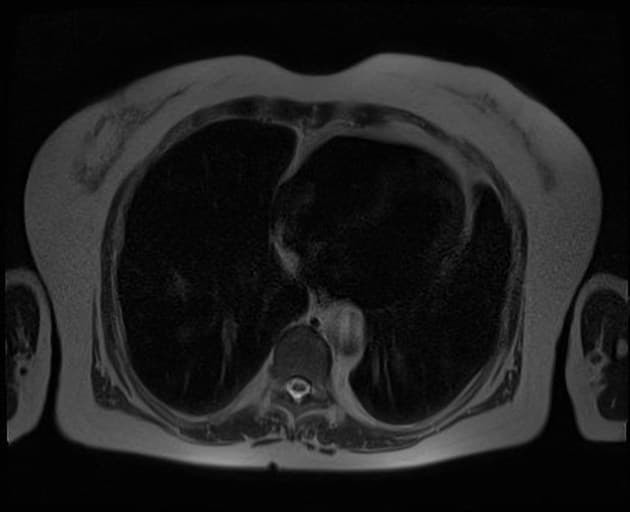

Axial T2

- Gan to với tín hiệu phù quanh cửa (periportal edema signal).

- Dày thành túi mật (mural thickening) và phù thành túi mật lan tỏa.

- Dịch ổ bụng (ascites) mức độ nhẹ.

- Ống mật chủ (common bile duct - CBD) và ống tụy có kích thước trong giới hạn bình thường, không thấy tổn thương gây tắc nghẽn.

Trong trường hợp vàng da, chụp cộng hưởng từ đường mật tụy (MRCP) có thể được sử dụng để đánh giá sỏi đường mật. Tuy nhiên, trong nhiều trường hợp, nguyên nhân do viêm gan virus cấp tính (vi rút viêm gan A). Các hình ảnh học thường gặp bao gồm gan to (hepatomegaly) với tín hiệu phù quanh cửa trên hình cộng hưởng từ trọng T2 (T2 WI). Dày thành túi mật lan tỏa và phù thành túi mật cũng là những dấu hiệu điển hình.

- "Ống mật và ống tụy bình thường trên MRCP giúp loại trừ nguyên nhân tắc nghẽn gây vàng da."

Viêm gan cấp, đặc biệt do virus viêm gan A, là nguyên nhân phổ biến gây vàng da và đau bụng ở các vùng lưu hành. Chẩn đoán hình ảnh đóng vai trò hỗ trợ, với cộng hưởng từ cho thấy gan to, phù quanh cửa (tín hiệu tăng trên hình trọng T2) và dày thành túi mật lan tỏa do viêm toàn thân và ứ trệ tĩnh mạch. Mặc dù MRCP thường được thực hiện để loại trừ tắc nghẽn đường mật, việc không thấy giãn ống mật hay tổn thương cản quang giúp khẳng định nguyên nhân không do tắc nghẽn. Xác nhận chẩn đoán bằng xét nghiệm men gan tăng và IgM kháng HAV hoặc PCR dương tính là cần thiết. Chẩn đoán hình ảnh giúp phân biệt viêm gan cấp với các nguyên nhân khác gây vàng da như sỏi ống mật chủ, khối u hoặc bệnh lý đường mật nguyên phát.